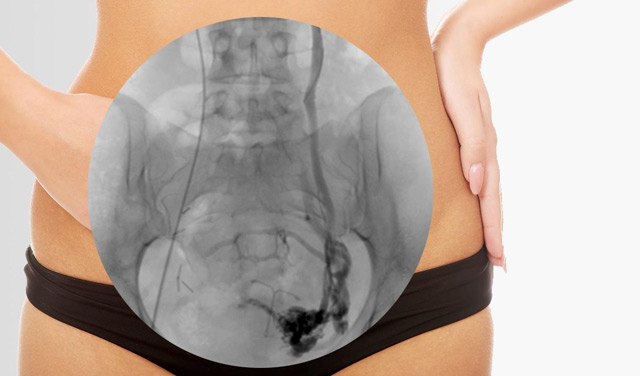

пример нацеленного введения рентеноконтрастного вещества

При наличии такой патологии, как варикозное расширение вен малого таза, встречающееся в основном у женщин, для уточнения диагноза может быть использована чрезматочная флебография. Варикозно расширенные вены чаще локализуются в области яичников и связок матки, а также могут привести к развитию осложнений – к тромбофлебиту и кровотечению. Именно поэтому так важно вовремя установить диагноз и начать лечение у пациенток с хроническими тазовыми болями.

Данное исследование основано на введении рентгеноконтрастного вещества в стенку матки, с последующим распространением контраста по венозной сети яичников и маточных труб. Благодаря исследованию врач может получить представление о клапанном аппарате вен, о скорости опорожнения вен от контраста, о наличии тромботических наложений в просвете вен малого таза при неинформативности ультразвуковых методов исследования. Поэтому чрезматочная флебография является дополнительным, а не основным методом исследования, и не применяется широко в рутинной практике врачей-гинекологов.

Чрезматочная флебография является инвазивным методом исследования, поэтому может вызвать определенный дискомфорт у пациентки. В процессе гинекологического осмотра “в зеркалах” в шейку матки вводится проводник, который продвигается до дна матки. Опасность перфорации (прободения) стенки матки будет практически сведена к нулю, если используются проводники из фторопласта, а не из металла. После достижения проводником дна матки через него вводится катетер с иглой на конце и осуществляется укол в маточную стенку не более, чем на 4 мм. Далее по катетеру вводится контраст (как правило, препарат кардиотраст), и уже через 10-20 секунд выполняются рентгеновские снимки с последующей их интерпретацией. В целом процедура занимает не более 30 минут.